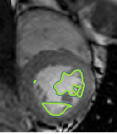

4.2 Visual assessment

We select the case that achieves the highest and lowest dice score for visual assessment. Fig. 4 shows example segmentation results where the proposed method achieved the highest agreement with the ground truth delineations. Fig. 5 shows example segmentation results where the proposed method achieved the lowest agreement with the ground truth delineations.

| (a) LV BG | (b) RV BG | (c) LV NM | (d) LV ME | (e) LV MS |